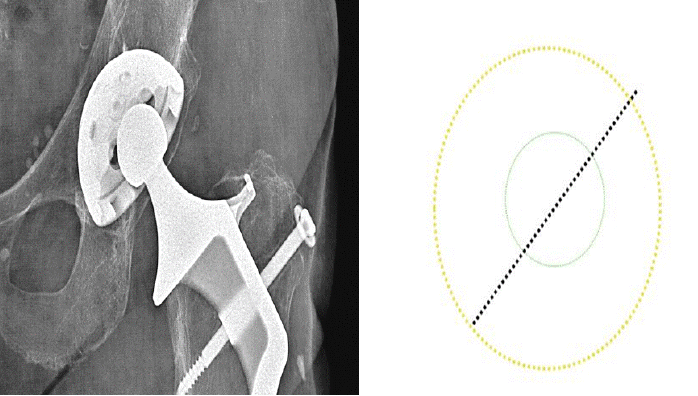

Eccentricity of the right metallic femoral head 0.7 cm loosening of polyethylene in 30 Years No calcar resorption, no screws fracture, periosteum inamovible apposition. Harris score: 100 (Figures 2-14).

Figure 13. 30 years follow up excentration of the head: 0.7 cm and ≠0.02 mm per year